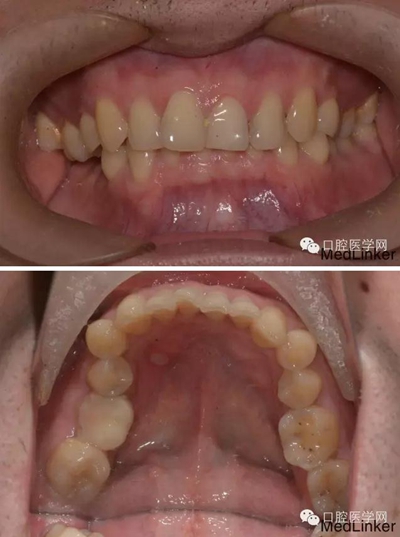

檢查:口內(nèi)恒牙列,上頜牙弓寬于下頜,右側第一磨牙第二磨牙正鎖合右下第一磨牙合面見大面積牙色充填物,牙面磨耗嚴重,咬合緊。

輔查:曲面斷層觀察齒c槽隔情況,為種植支抗植入熟悉解剖。